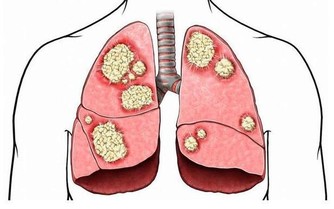

目前中國有1億人左右患有靜脈曲張,靜脈曲張的問題不僅僅是看上去不雅觀,更重要的是,當靜脈曲張累積到深靜脈時,或引起肺栓塞,導致猝死。

所以我們應該對靜脈曲張保持足夠的警惕,及時干預,防止出現深靜脈血栓,增加猝死的風險。因此,今天,我們主要講講靜脈曲張的預防。

以上方法的核心思想就是收縮小腿肌肉,促進血液回流,如果你有其餘的辦法也能達到這種效果,也可以一試。在這裡,主要是給年輕人們提個醒,如果你現在就發現自己有靜脈曲張,一定要加以重視,及時干預,將肺栓塞的可能性降到最低。